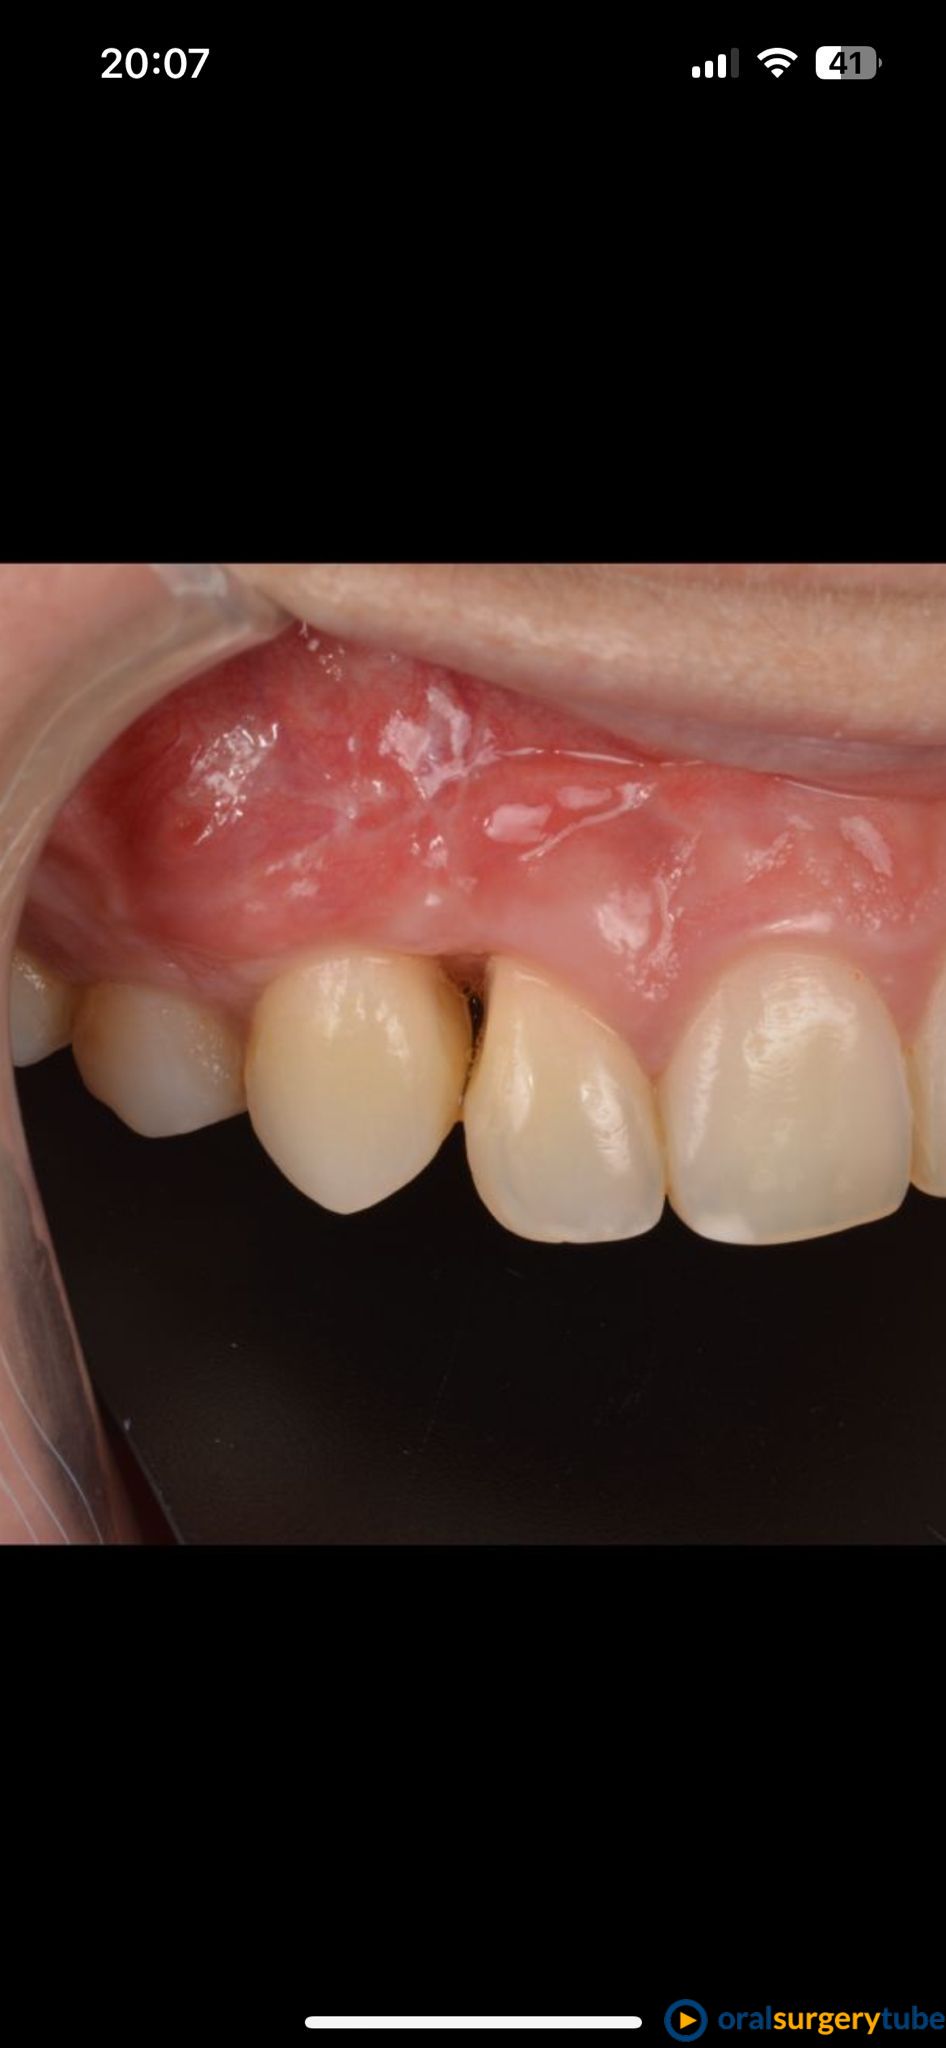

Seguimiento de caso de defecto vertical entre dos dientes (12 y 13) tras cirugía ortognática.

Paciente de mediada edad que es remitida para intentar mejorar el estado periodontal de los dientes 12 y 13 tras cirugía ortognática. A la paciente le habían realizado previamente varios injertos de tejido conectivo y empleo de Emdogain® sin éxito. Se plantea hacer técnica de Wall technique de Zucchelli modificada para simultanear técnicas de regeneración ósea guiada.